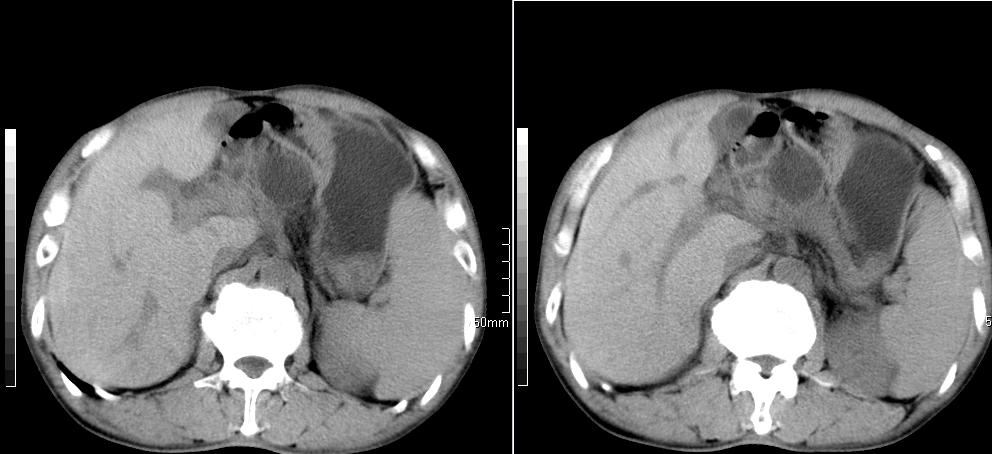

标题: CT26769:男,58岁,腹胀、腹部不适一年余 [打印本页]

标题: CT26769:男,58岁,腹胀、腹部不适一年余

肠系膜脂膜炎,胆囊炎,脾大。建议结合临床。鉴别:慢性胰腺炎并假囊肿形成。

1 慢性胰腺炎并假囊肿形成。2 慢性胆囊炎并累及肝边缘!

1)考虑慢性胰腺炎并假性囊肿形成。2) 慢性胆囊炎。3)肝内胆管扩张。

支持1 慢性胰腺炎并假囊肿形成。2 慢性胆囊炎。

1肝内胆管扩张,性质待定,2慢性胰腺炎胰管扩张,胰腺颈部假囊肿,3肝左叶低密度为小囊肿,4胆囊炎。